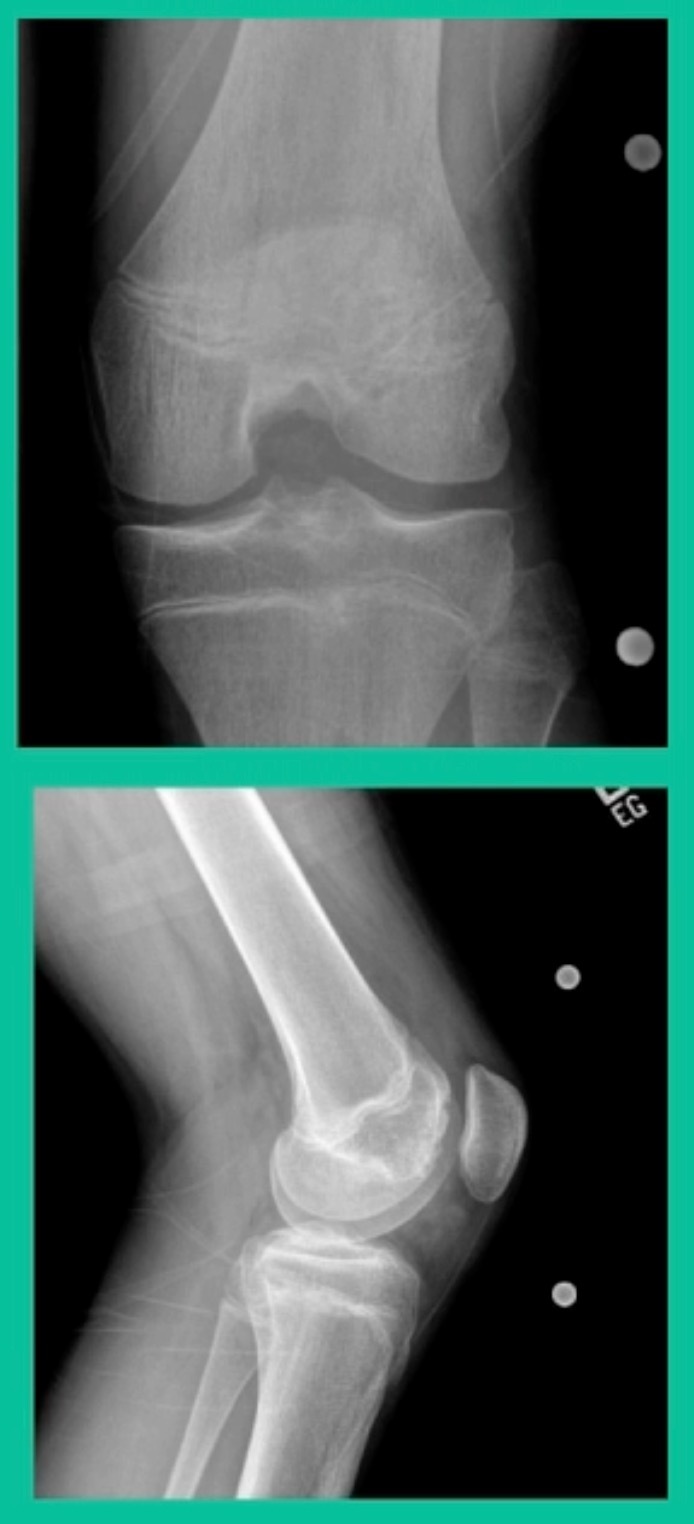

Now, we’ll shift to the adult. This is a 27-year-old. Right knee swelling, activity-related, and classic failed nonsurgical treatment on the lateral side of the knee.

This will probably be fixed. It’s a big piece and we’ll try to preserve it. The literature shows that preservation does pretty well. In this instance, there’s very little bone. It’s somewhat dystrophic, not very encouraging in my mind.

43-Year-Old, symptomatic medial femoral condyle.

D1 football player formally, affecting ADLs. For this one, I initially just wanted to watch it. This looks pretty small when he came in. Let’s see what happens. Six months later, this is where he progressed to.

This is an 18-year-old with a lateral femoral condyle OCD: